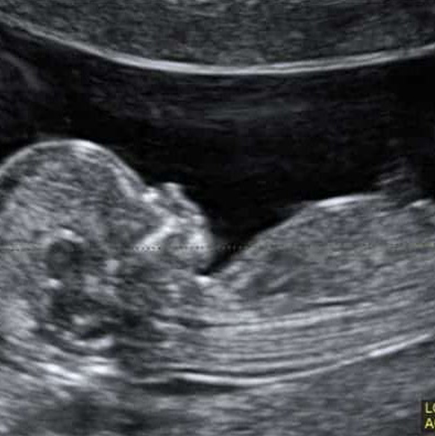

שקיפות עורפית

יש לעשות בין השבוע ה־11 לשבוע ה־13 ו־6 ימים להיריון

בדיקת שקיפות עורפית היא בדיקת אולטרה סאונד המבוצעת באשה הרה, לצורך הערכה סטטיסטית של הסיכון לתסמונת דאון בעובר